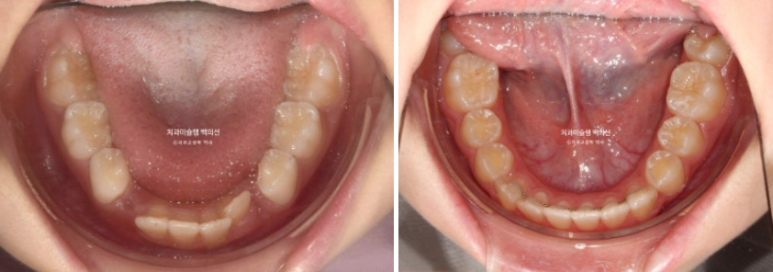

아랫니도 공간이 많이 부족합니다.

골격분석상 하악골 여성장을 동반한 무턱으로 진단되어 치료 목표는

악궁확장을 통한 덧니 해소

MA 기능으로 하악성장 유도

이 두가지가 되겠습니다.